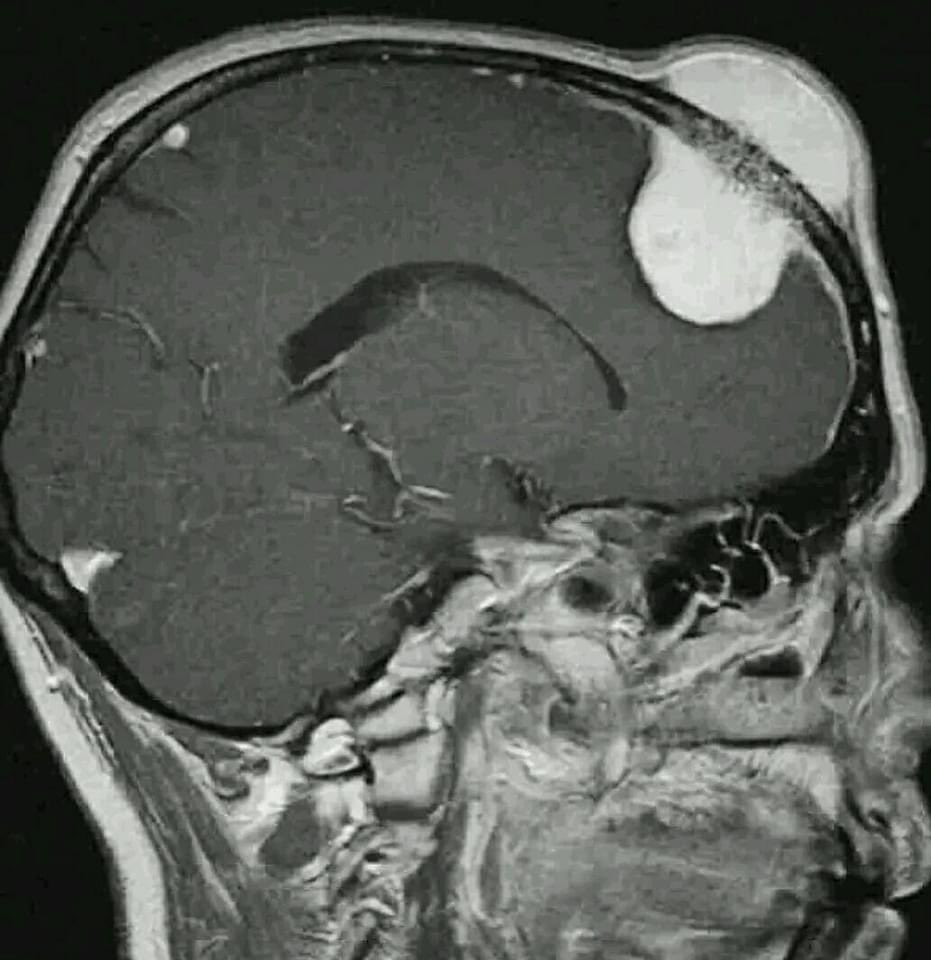

- 58-year-old female with vaginal bleeding for the past 2 months - findings and diagnosis ? #MEDHM @IhabFathiSulima #MedEd #MedX

hemo_shk's tweet image. - 58-year-old female with vaginal bleeding for the past 2 months

- findings and diagnosis ?

58-year-old female with active vaginal bleeding #Findings: •There is thickening of the endometrium measuring 14mm in thickness with internal intermediate signal intensity seen. •The lesion is seen extending into the myometrium with invasion of the serosa layers. •The lesion

#Findings:

•There is thickening of the endometrium measuring 14mm in thickness with internal intermediate signal intensity seen.

•The lesion is seen extending into the myometrium with invasion of the serosa layers.

•The lesion